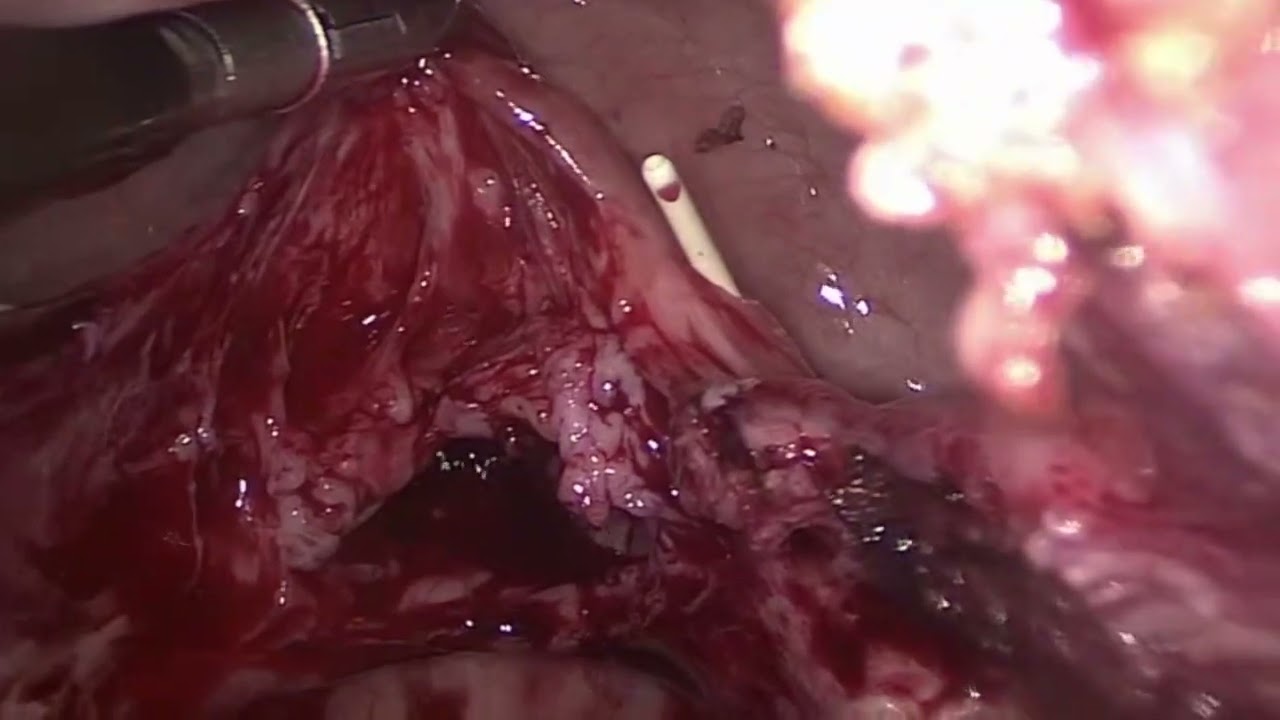

Sou especializado em tratamento minimamente invasivo de cânceres urológicos como os de próstata e de rim, por técnicas minimamente invasivas, mais notadamente por cirurgia Robótica e Videolaparoscópica. Me dediquei intensamente à Urooncologia nos últimos 9 anos, ja tendo operado e ajudado mais de 600 pacientes oncológicos neste período, sempre mantendo um atendimento humanizado e ético, que todo o paciente oncológico necessita.

• cirurgia robótica

• Cirurgia robótica da próstata